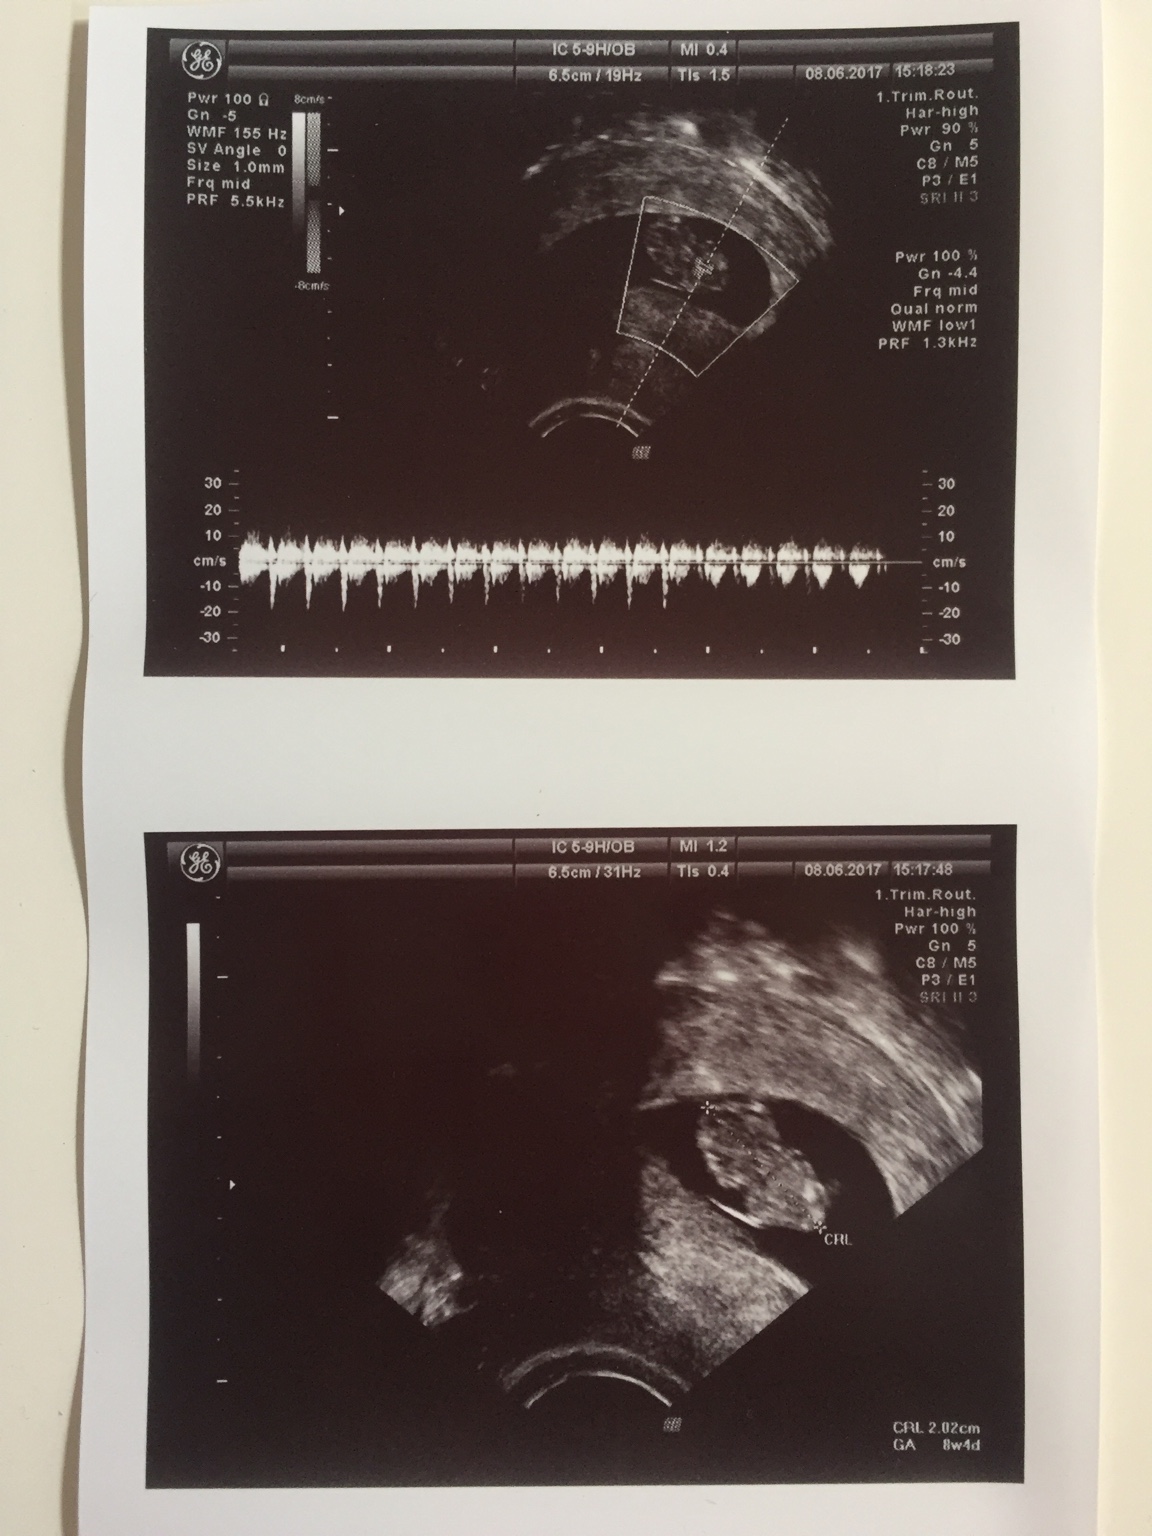

Ja już po wizycie, wszystko z dzidziulkiem w porządku, mierzy 2.02 cm, serduszko słodko pikało i dzidziuś się ruszał (choć ja nie umiałam tego dostrzec[emoji16]). Waga u mnie 0.70 na plusie, mdłości i wymiotów nadal zero. Ciśnienie niskie 96/74 stad to moje ciagle zmeczenie i senność